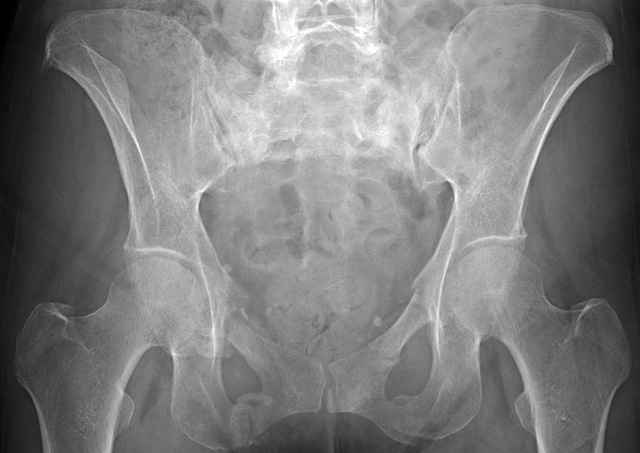

Here are a recent patient’s example slides...

54 yo Female Fell c/o Pain

Initial Films

?Instability on Exam - Limited by Pain

NonOp Initial Mgmt

Sacral Injuries

Ramus Fractures